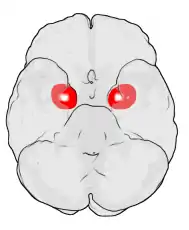

Frontal and side view of amygdala

Amygdala along with other subcortical regions, in glass brain.

Dorsal view of the amygdala in an average human brain

Frontal view of the amygdala in an average human brain